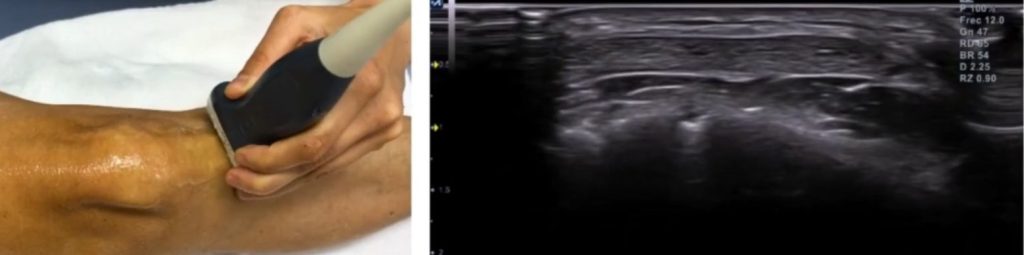

Cómo explorar el tendón rotuliano con ecografía

El corte de referencia longitudinal, incluirá las corticales de la tuberosidad tibial anterior y el polo inferior de la rótula.

Cuando más lateral o medial se haga el corte, más fino será el tendón.

Una vez exploradas las estructuras en longitudinal, pasaremos a un corte transversal.

En este corte deberás hacer un barrido de craneal a caudal para explorar el tendón en toda su longitud.

La zona más frecuentemente afectada en la tendinopatía es la inserción proximal, precisamente en los primeros 1-2 cm desde el polo rotuliano.

El corte transversal será fundamental para confirmar o descartar posibles signos patológicos que hayas detectado en el corte longitudinal.